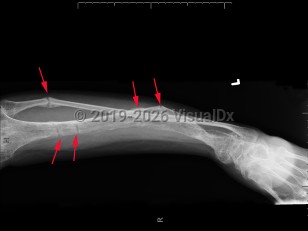

Familial hypophosphatemic rickets is a group of familial disorders characterized by hypophosphatemia and rickets as well as resistance to physiologic vitamin D repletion. The most common of these is X-linked hypophosphatemic rickets (XLH), in which an inactivating mutation leads to elevated serum fibroblast growth factor 23 (FGF23) levels, resulting in renal phosphate wasting. Sometimes the condition can arise from a spontaneous mutation.

Clinical presentation is variable and typically presents after 18 months of age or when the pediatric patient begins to walk. Symptoms range from growth retardation and short stature to severe rickets or osteomalacia. Some patients have isolated hypophosphatemia detected on serologic testing. The typical presentation is a child with leg bowing and other bone deformities, pseudo-fractures, bone pain, and short stature. Rarely, a patient may present with tetany, dental enamel defects, and spine or pelvic rickets.